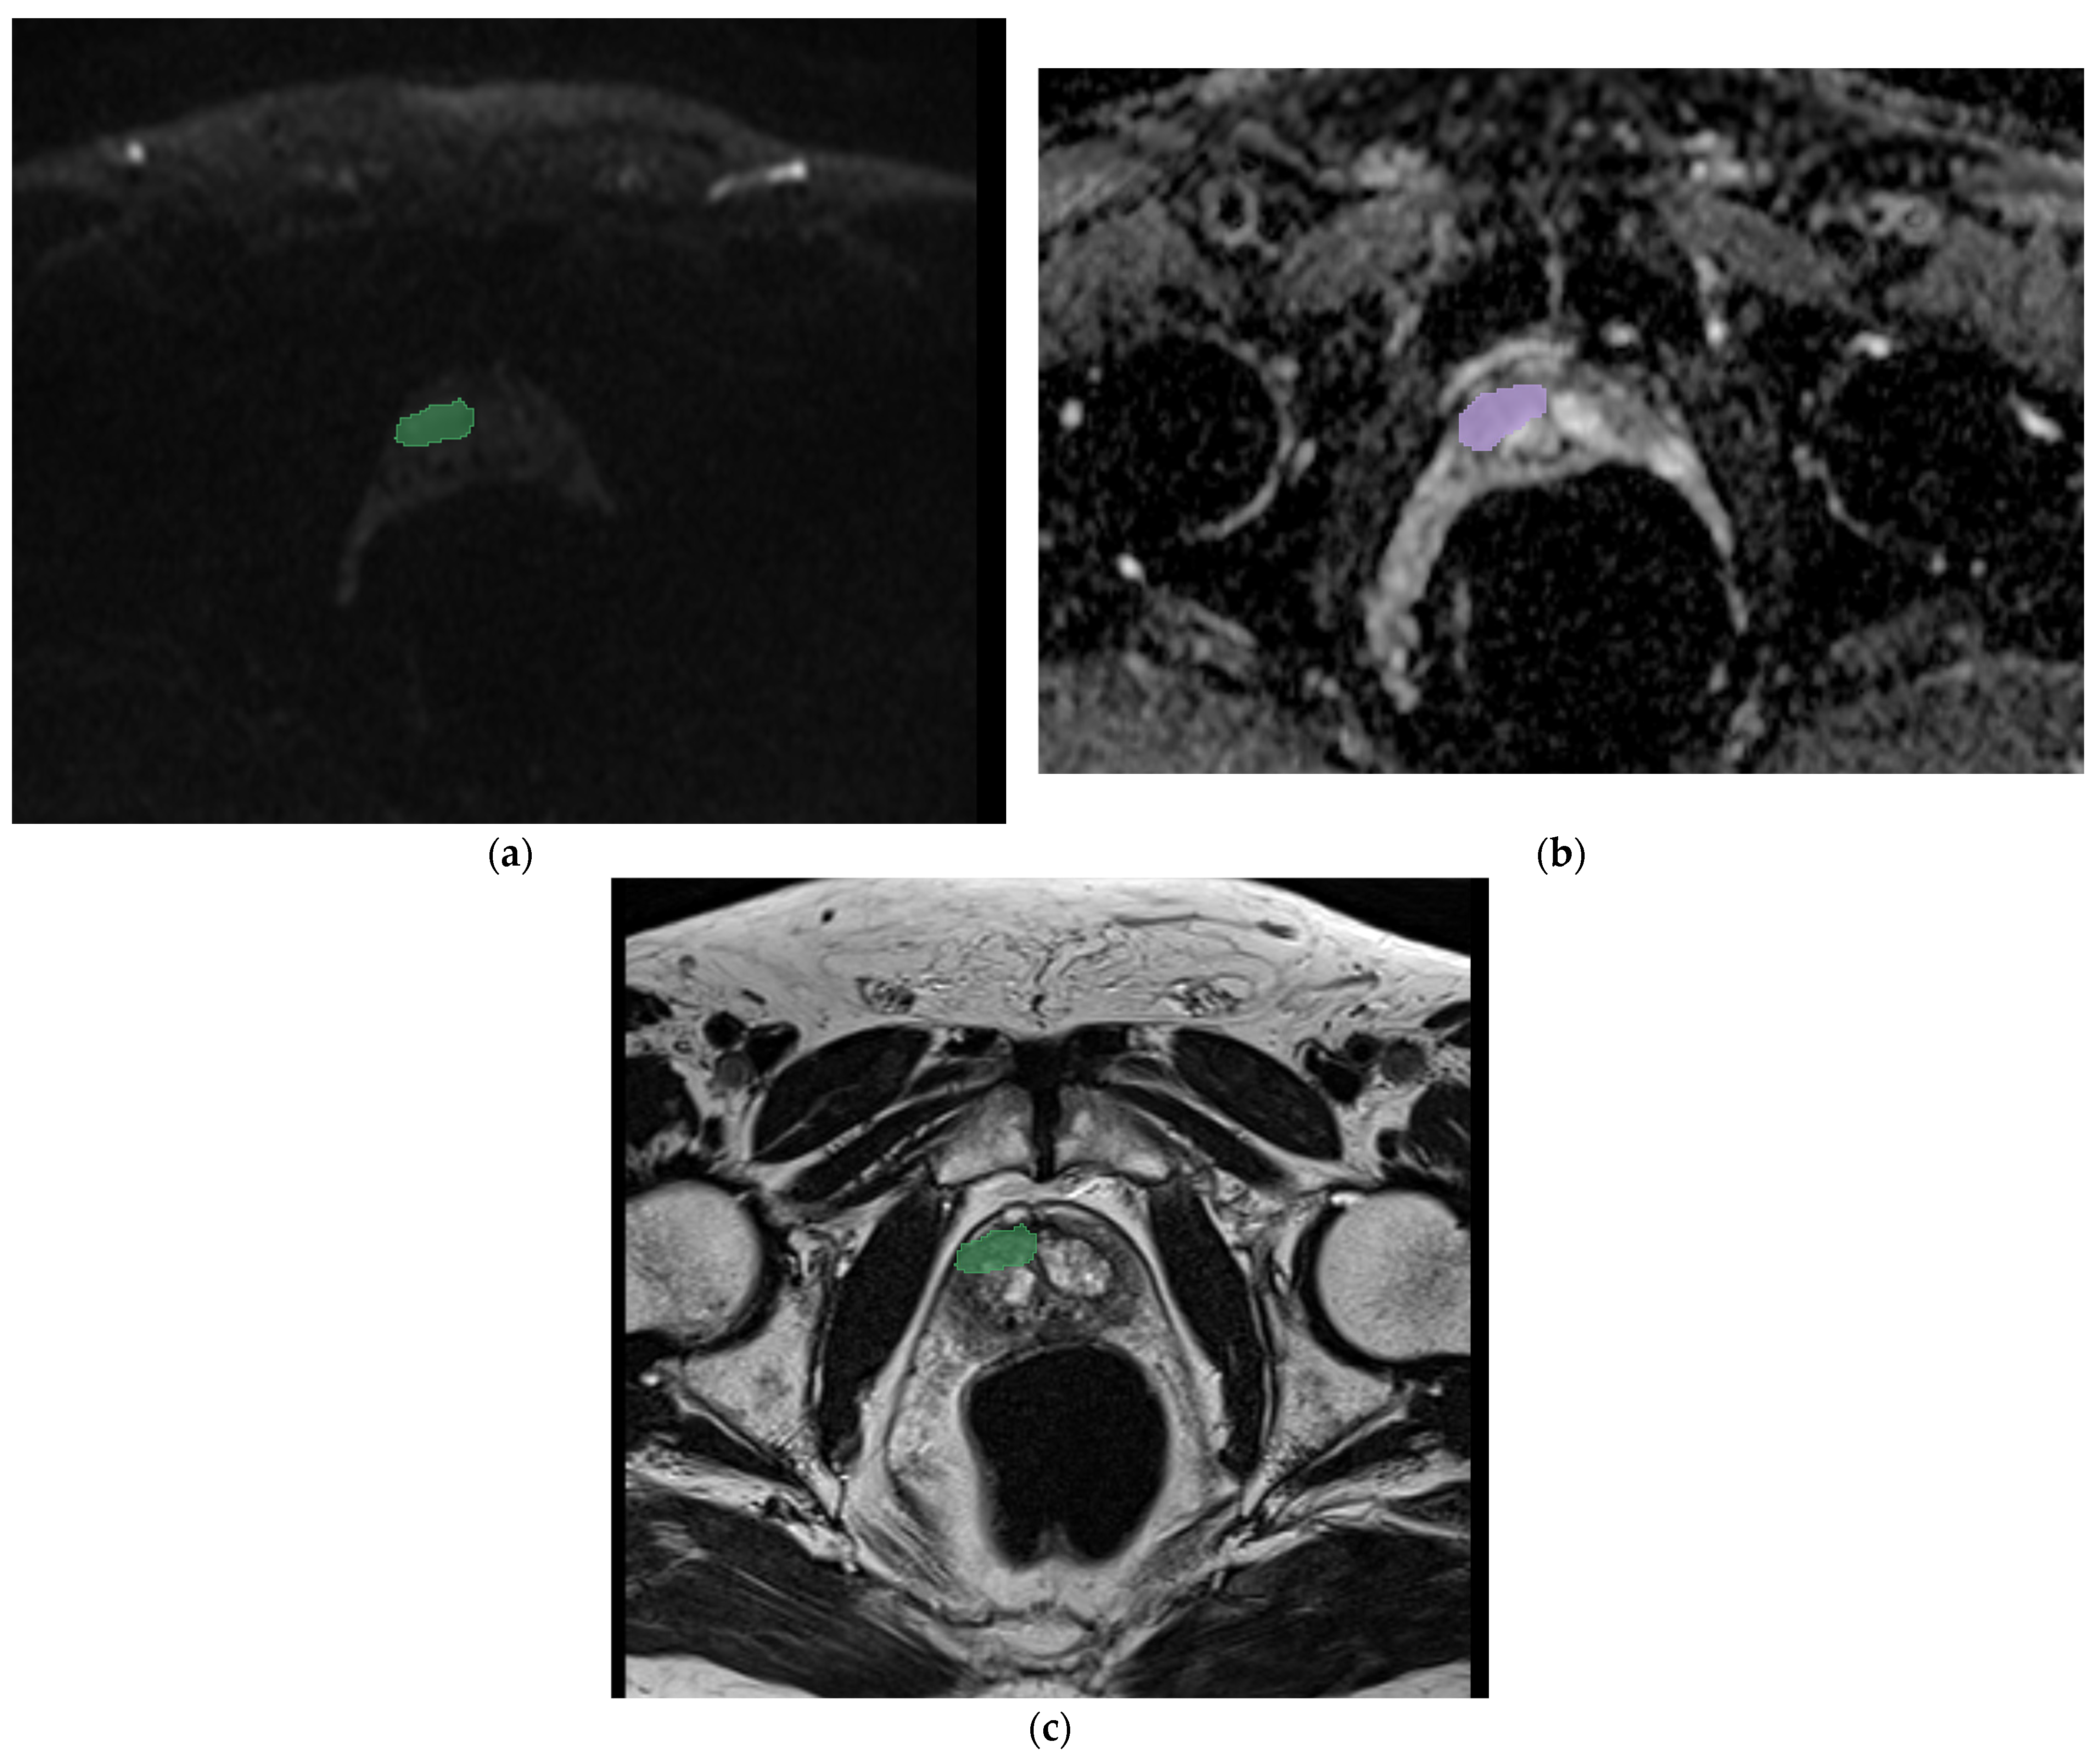

2.2. Segmentation, Feature Extraction